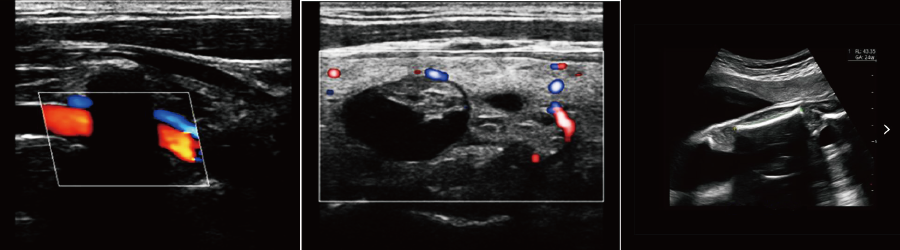

便攜式彩超機臨床圖

DW-PF582便攜式彩超效果圖